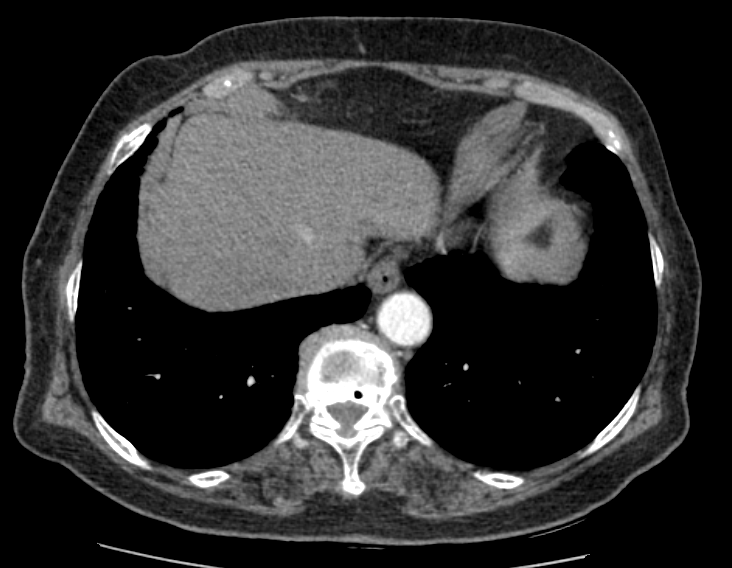

F/73

DM, HTN °ú°Å·Â ÀÖ´Â ºÐÀ¸·Î hip osteoarthritis ·Î THR ½ÃÇà ¿¹Á¤ÇÏ´ø Áß preop CXR abnormality ·Î ÀÇ·ÚµÊ.

never smoker, Á÷¾÷ : ¹«

Cough/Sputum (-/-)

Dyspnea/DOE (-/-)

CBS s rale

wheezing (-)

< Chest CT >